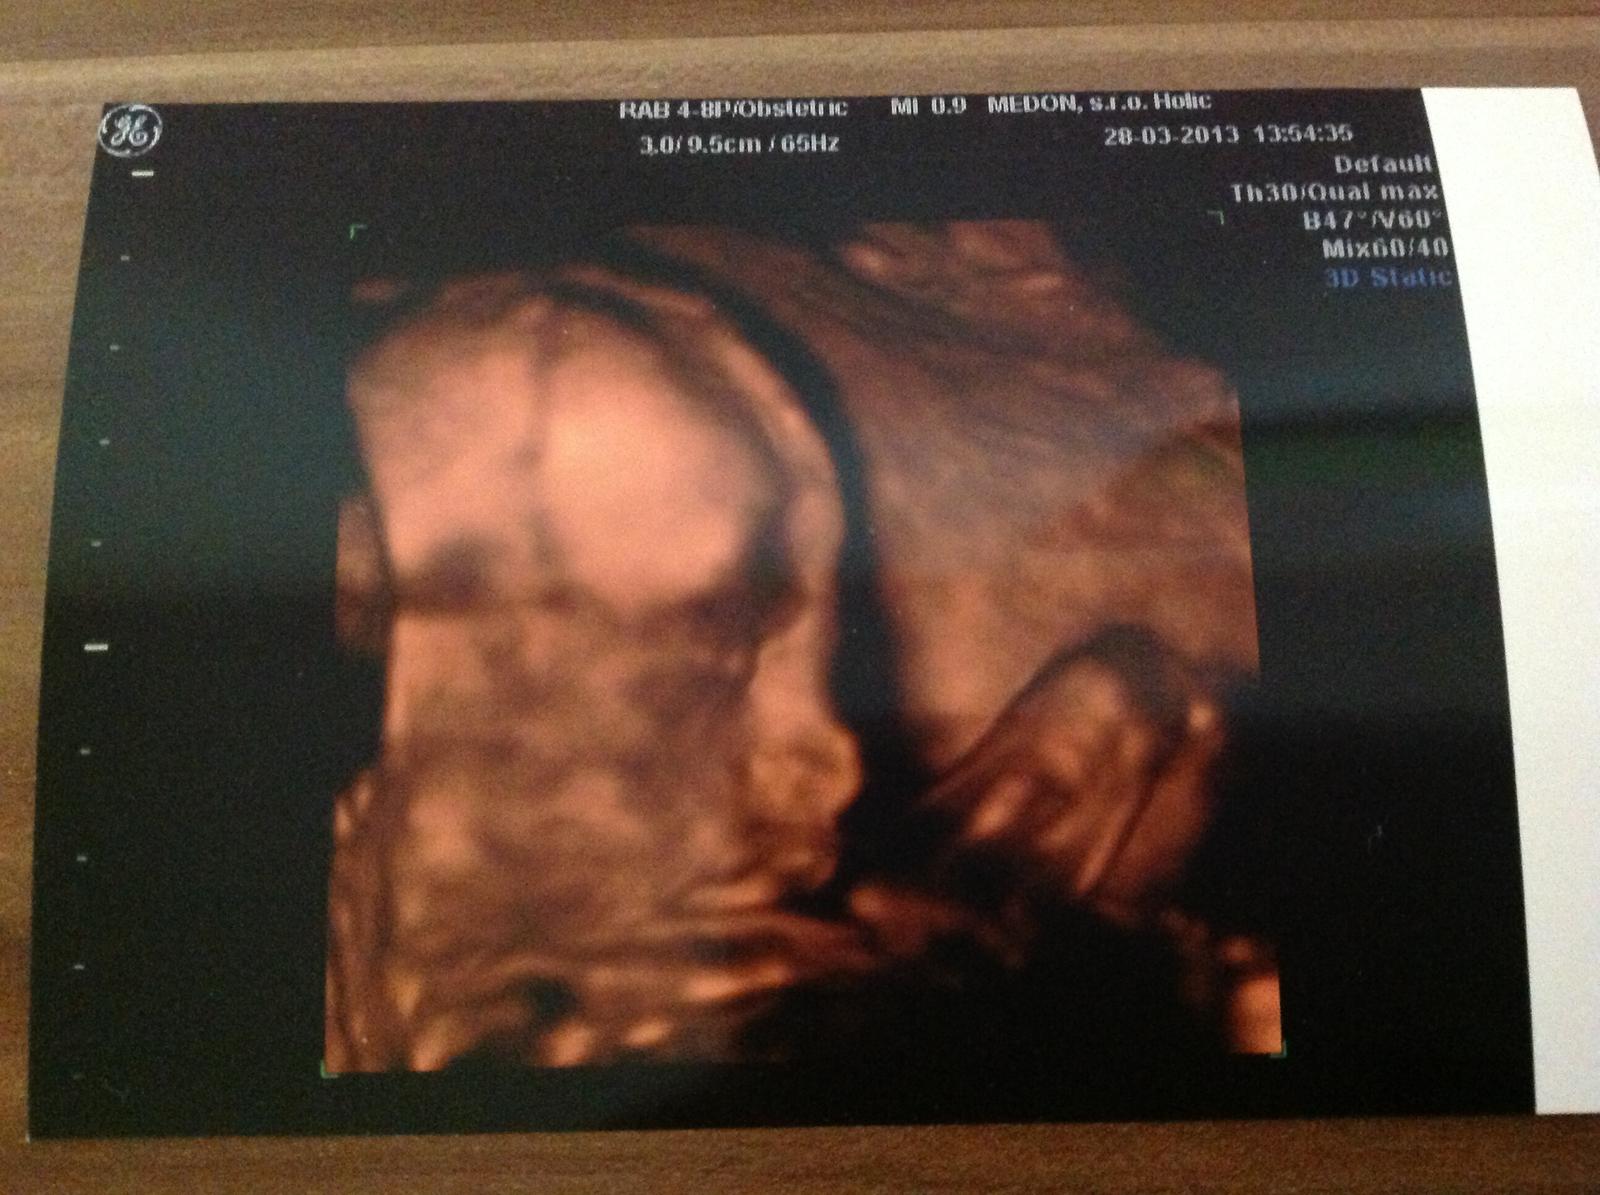

Ahojte kocky mi sa tiez pridavame termin mame 12 augusta. Pretrpeli sme si stresy pretoze nam vysiel vysledok z krvi 1:7 DS isla som na amnio kde nam koli takemu vysokemu skore dali vysledky do 3 dni na 5 najcastejsich chromozomov zatial je vsetko v poriadku ostatne chromozomy vysetria do konca buduceho tyzdna. Co vam budem hovorit darmo Vam povie niekto nestresuj sa ked ide babo.